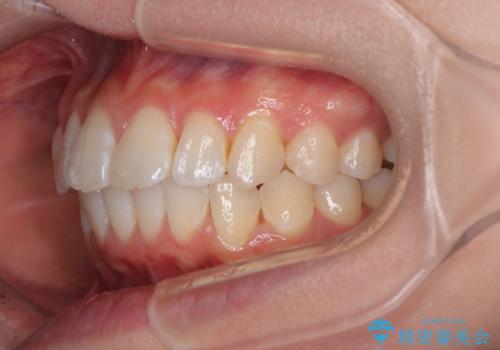

深い咬み合わせによる隙間 インビザライン矯正でコンプレックスを改善

- 上の前歯の隙間を気にして来院された患者様です。

インビザラインにより、上下の歯列を側方に拡大しつつ、前歯の隙間を閉じていくこととしました。

隙間の原因は強い咬合力や舌の突出癖、小帯の異常付着などがありますが、舌のトレーニングをしっかりと行いながら、装着時間を遵守して装着していただいたおかげで、スムーズに治療を終えることができました。